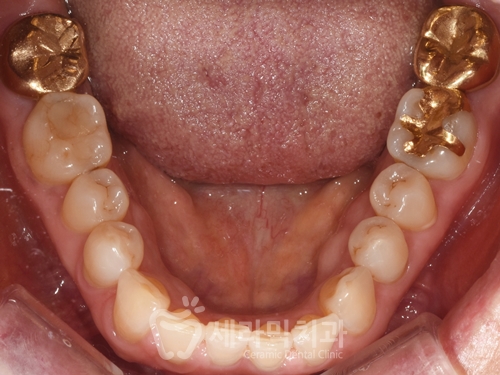

(2) 문제점 분석, 진단

① 치열불규칙

② 앞니 반대교합

③ 아래턱 돌출 경향

(3) 치료방법

치아배열 개선과 위쪽 앞니를

바깥쪽으로 이동하는 것을 목표로

"비발치교정"을 하는 것으로 진단하였습니다.

위 아래 반대교합으로 인해

교정 브라켓이 부딪히는 것을 막기 위해

특수 장치인 'Posterior Bite Plate'를 장착합니다.